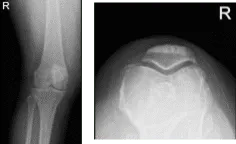

She presented her Xray results, for her left knee there are mild osteoarthritic degenerative changes. For the right knee, there are moderate osteoarthritic degenerative changes. There are no fractures and there are no acute fractures.

Left knee X-ray

Right knee X-ray

XR of Right Knee Lateral Oblique View